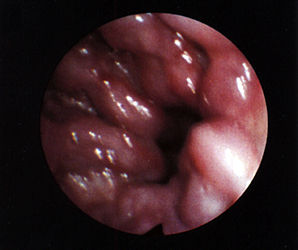

食管靜脈瘤呈青藍色或紫藍色圓形或卵圓形扁平狀隆起,表面黏膜完好,無新近或陳舊性出血灶,無搏動,邊界清楚,如無食管合併症,則周圍食管黏膜無異常;如靜脈瘤為多發性,則各個靜脈瘤之間有正常食管黏膜間隔而非連續性;如與食管靜脈曲張並存,其間也間隔有正常食管黏膜;食管靜脈瘤無出血、潰瘍、癌變等,也不引起食管解剖或功能性狹窄,屬良性病變。

一般使用內鏡診察,此外還可進行CT診察、超聲內鏡診察(Endoscopicultrasonography:EUS),以觀察其引起出血的可能性、詳細狀態、判斷治療效果等。通過內鏡診察來觀察食管靜脈瘤的出血、糜爛以及周圍的血管等,並以此決定治療方針。

內鏡下靜脈瘤結紮術:是使用內鏡將食道靜脈瘤綁紮並除去的方法。與EIS相比,給患者帶來的痛苦較少、簡便安全,但是治療後復發的可能性較高。